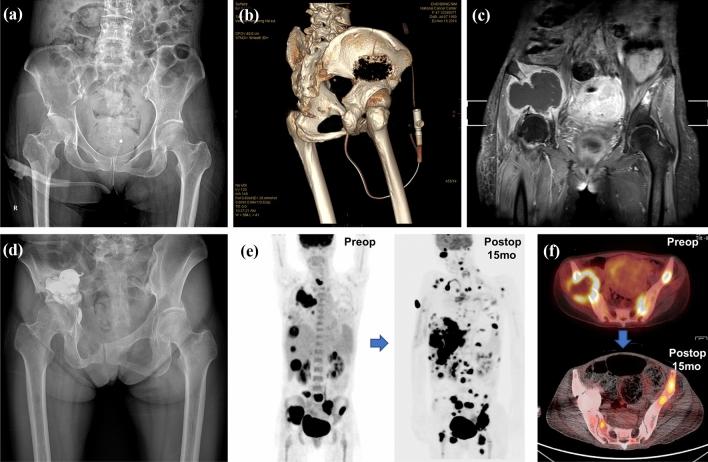

In advanced cancer patients, pelvic bone metastasis often causes pain and gait disturbance. The use of percutaneous bone cement [polymethylmethacrylate (PMMA)] injection for pain management and strengthening in pelvic bone metastasis has rarely been reported. To evaluate this method, we aimed to determine surgical outcomes and complications over a long-term follow-up period using a large patient group.

We retrospectively collected data from 178 patients who underwent percutaneous cementoplasty for pelvic metastatic lesions, 201 in total. Surgical outcomes evaluated included pain reduction and improvement of ambulation. Mortality within 1 month after procedure and pulmonary embolism caused by thrombus, fat, tumor emboli, or bone cement were investigated as surgical complications. For long-term survivors, pain relapse and mechanical failure were analyzed. The mean follow-up period was 12.6 months, and there were 159 fatalities at last follow-up.

The mean regional pain numerical rating scale scores decreased from 6.1 preoperatively to 2.4 1 month after procedure (p < 0.01). Gait function was maintained, worsened, and uncheckable in 68%, 24%, and 8% of patients, respectively, 1 month after procedure. Of long-term survivors followed up for > 12 months (n = 53), there were no significant changes in serial plain radiographs, and regional pain aggravation was observed in 9%. Pulmonary cement embolism and bone cement implantation syndrome was observed in 11% and 10%, respectively. However, all patients with these complications were asymptomatic.